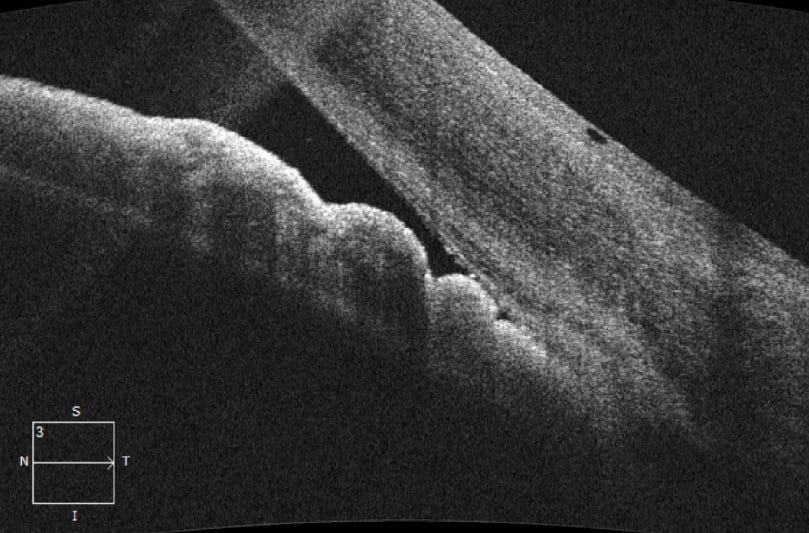

Caption: An anterior segment OCT showing a closed angle